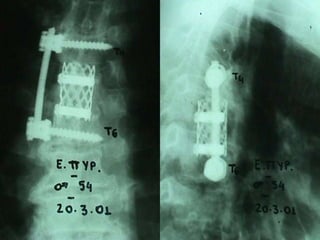

3rd case

EV. PY.

M 56 – Industrial labor

Follow up

Pus culture

(staphylococous aureous)

Antibiotics

 i-v for 2 mts

 orally for 6 mts

Complete neurologic recovery

3rd case EV. PY. M56 – Industrial labor Symptoms  Neurologic deficit  Thoracic Pain  Low fever Laboratory  Neutroph. ↑  SR 45